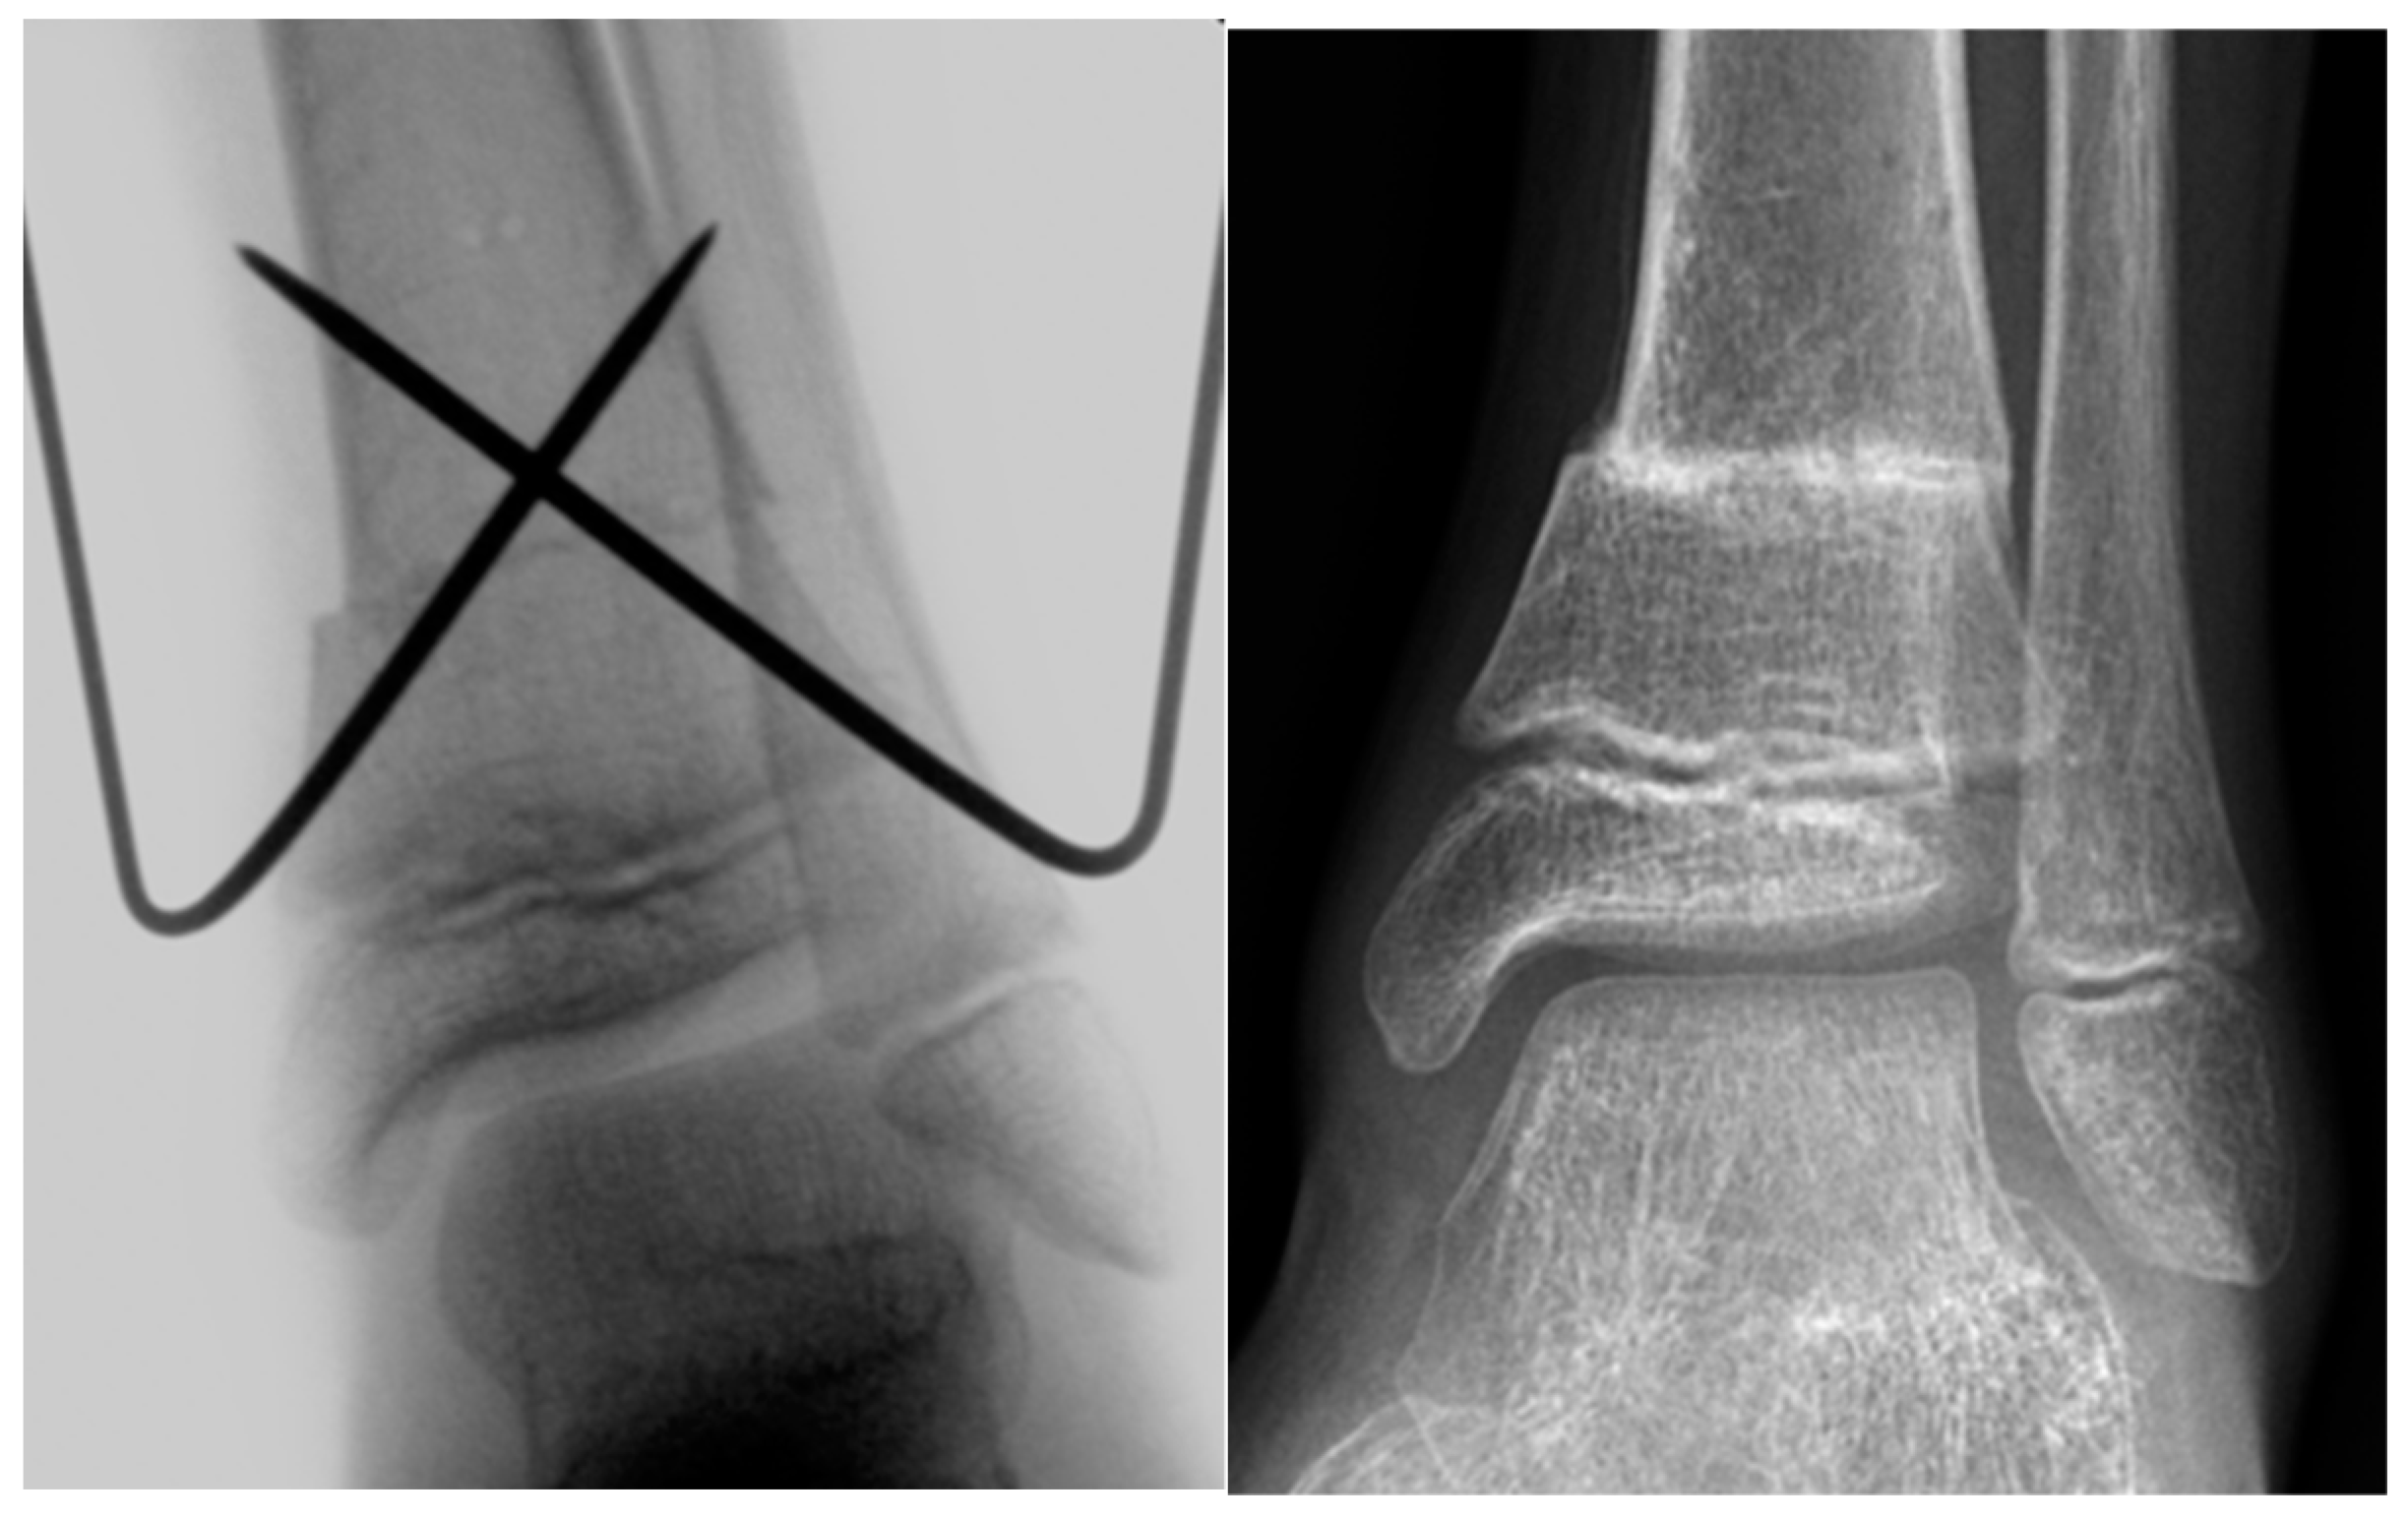

De Roode et al. reported higher rates of complications in patients who underwent plate fixation of SMO [13]. The authors applied crossed K‑wire stabilization followed by postoperative cast immobilization of the lower leg as well as SMO fixation with nonangular stable plates, followed by lower-leg cast immobilization. At our institution, we use both K-wires (Figure 1) and locking compression plates (LCP; Figure 2) to stabilize SMOs in children.

Figure 1. Intraoperative X-ray image and X-ray image obtained at 2 months after SMO fixed with K‑wires in an 11-year-old male patient with increased external torsion of the tibia.